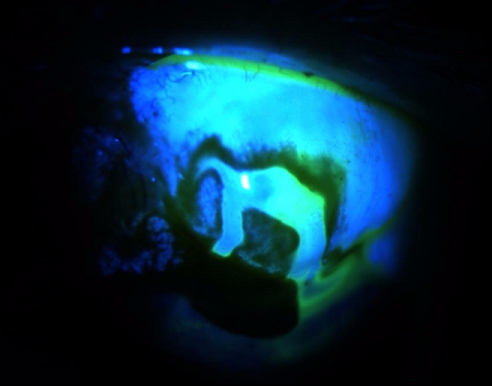

여과포염(blebitis)이 발생하게되면,

초기증상은 bleb주위의 미미한 정도의 결막 충혈이 관찰됩니다.

이때쯤부터 환자는 충혈과 함께 눈불편감, 시력 저하를 느끼게 됩니다.

초기에 호전되면 괜찮으나, 진행하게되면,

결막충혈이 증가하면서 여과포가 주변의 충혈된 혈관에 대비되어, 우윳빛 모양으로 보기에됩니다. 이를 white on red appearance 라고 합니다.

역시 눈불편감, 둔통, 시력저하 등의 증상들이 더욱 심하게 나타납니다.

더욱 진행하게되면서 여과포 주위의 감염이

안구내부로 침투하게되면 이내 안구속에 감염이 발생하는 상태인

안구내염, 안내염(endophthalmitis, Bleb associated Endophthalmitis)이 발생하게됩니다.

이때는 전방에서 염증세포들이 관찰되기 시작하면서,

안구내에 심한 경우 안구내에 전방축농이 관찰되기도 합니다.